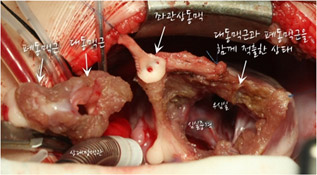

[사진1] 대동맥 뒤에 위치한 폐동맥이 관찰됨. 폐동맥 자체가 작고 이엽 판막임. 대혈관치환술 하기에는 폐동맥 판막의 모양이 좋지 않음.

-

[사진2] 폐동맥근과 대동맥근을 한꺼번에 떼어낸 뒤 360도 회전해서 다시 연결한다.

-

[사진3] 심실에서 분리한 폐동맥과 대동맥근